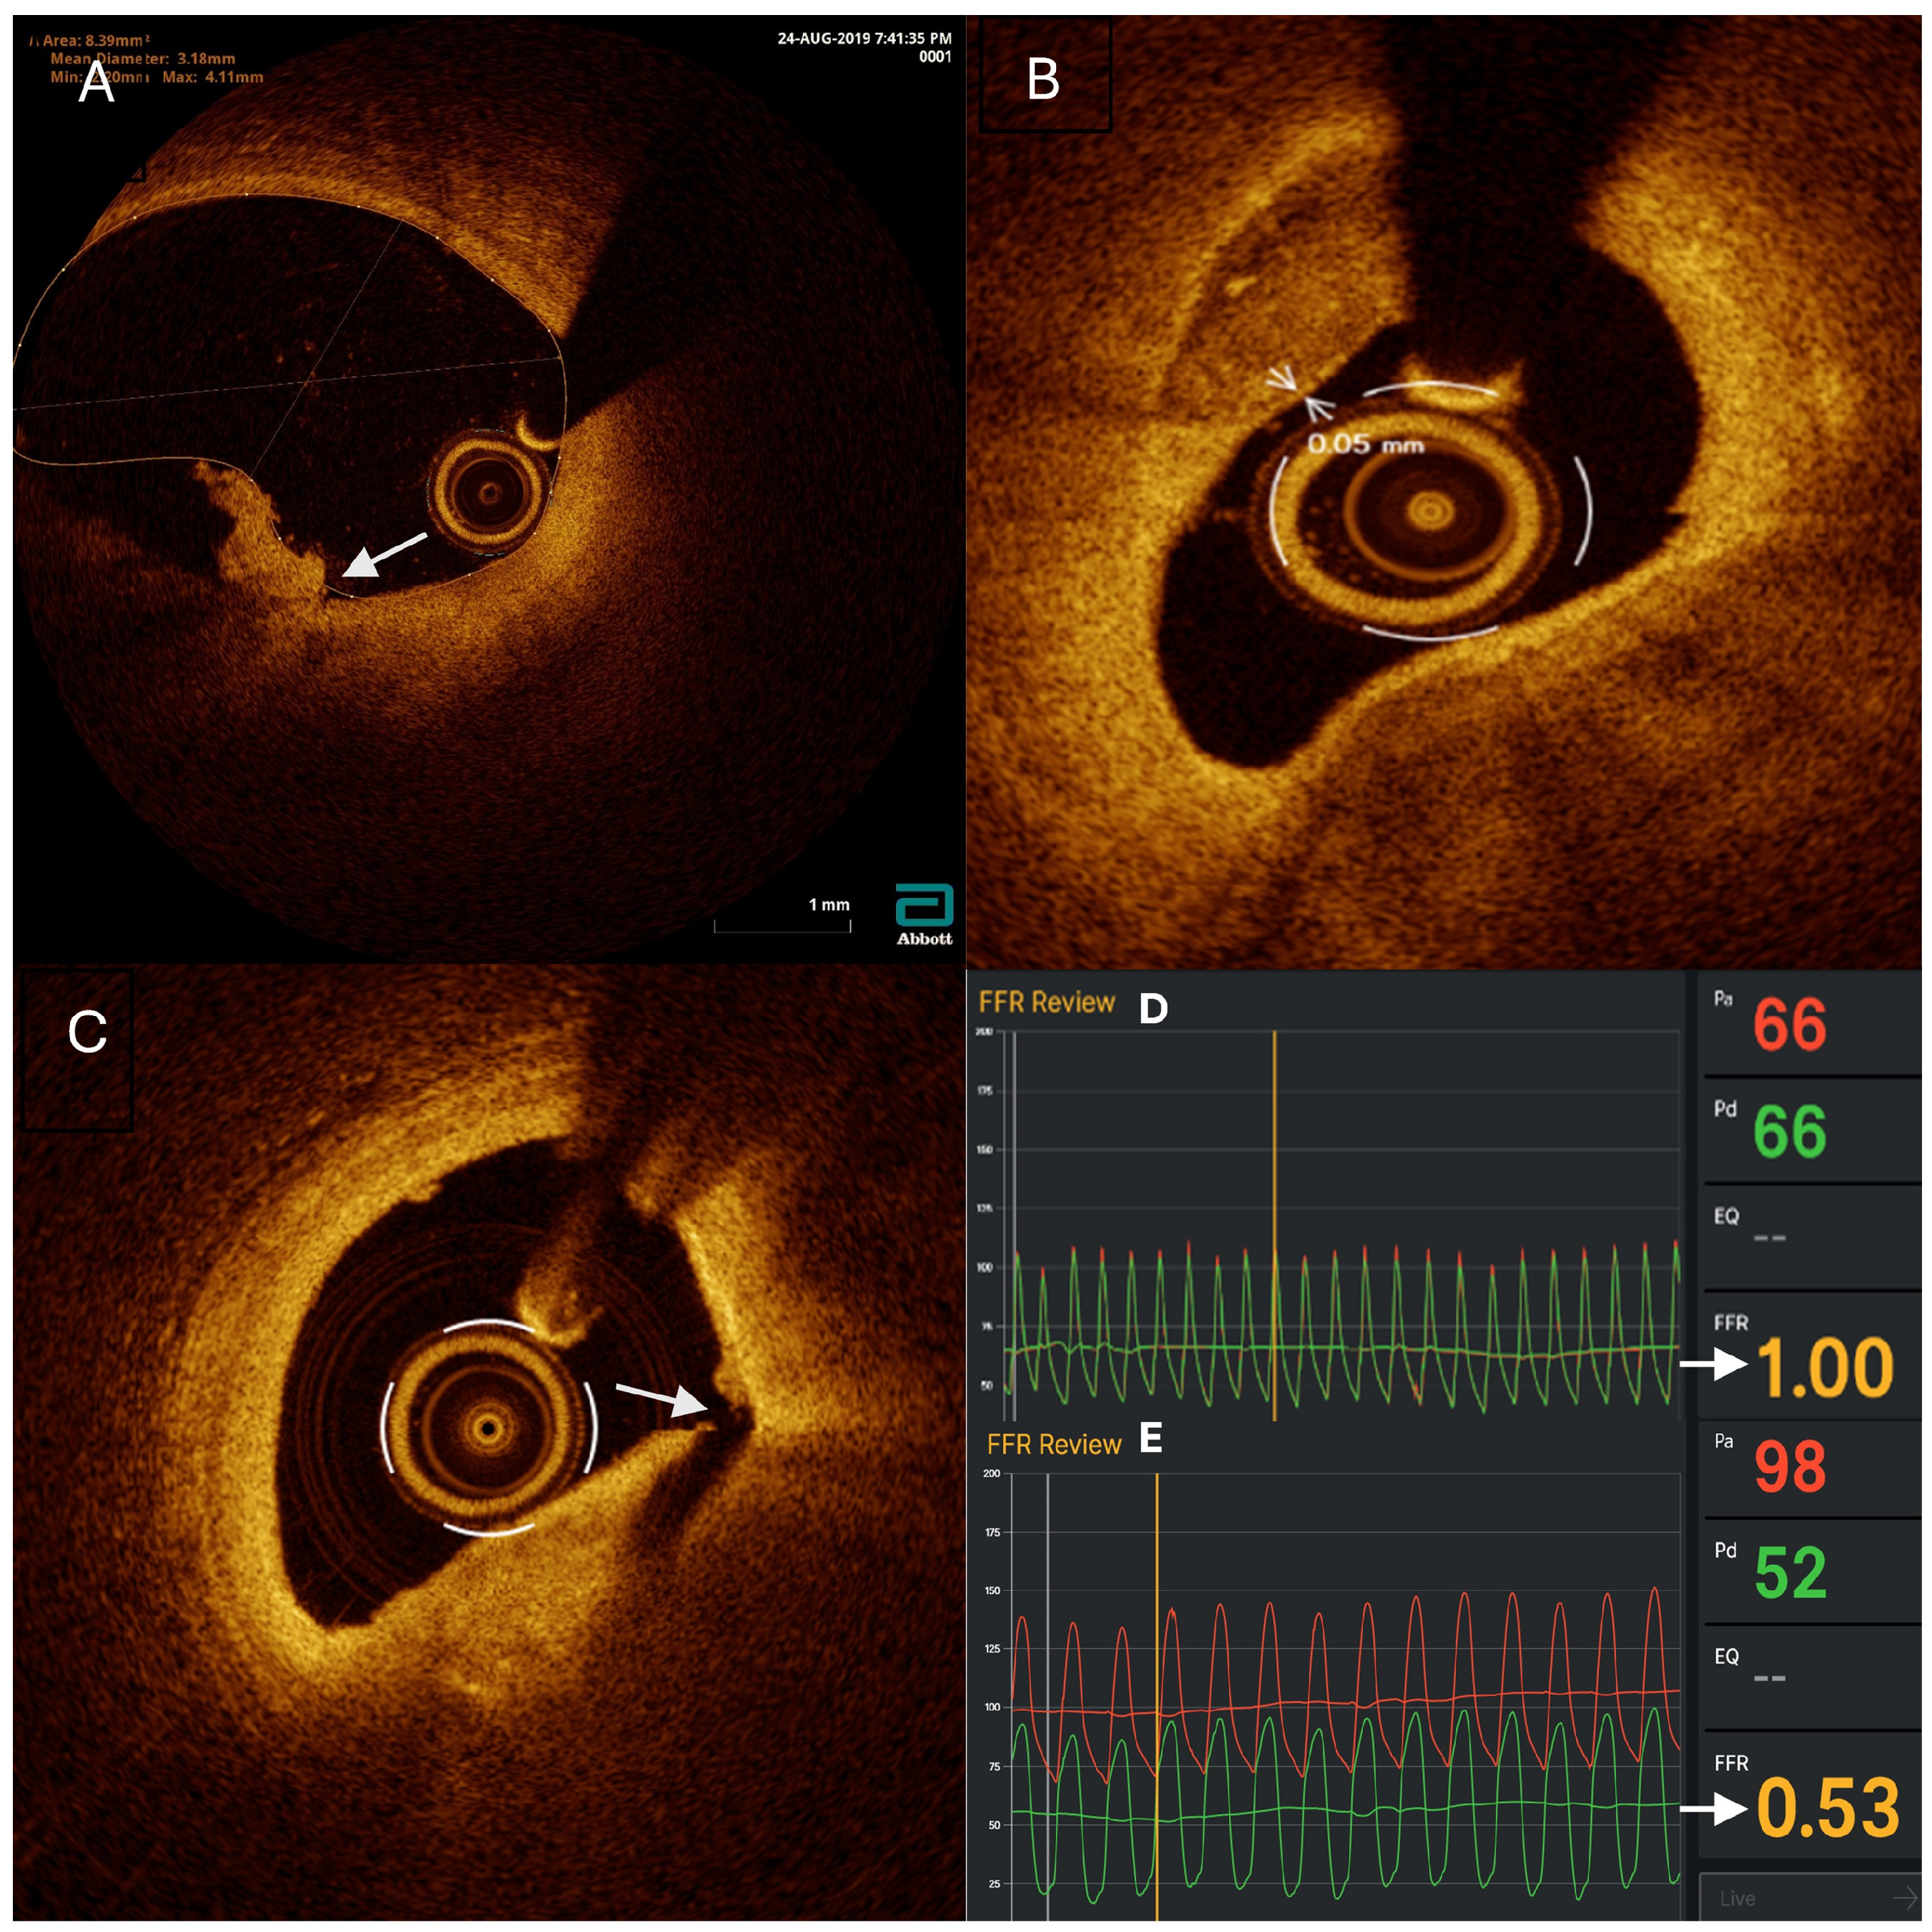

3.2. Figures, Tables, and Schemes